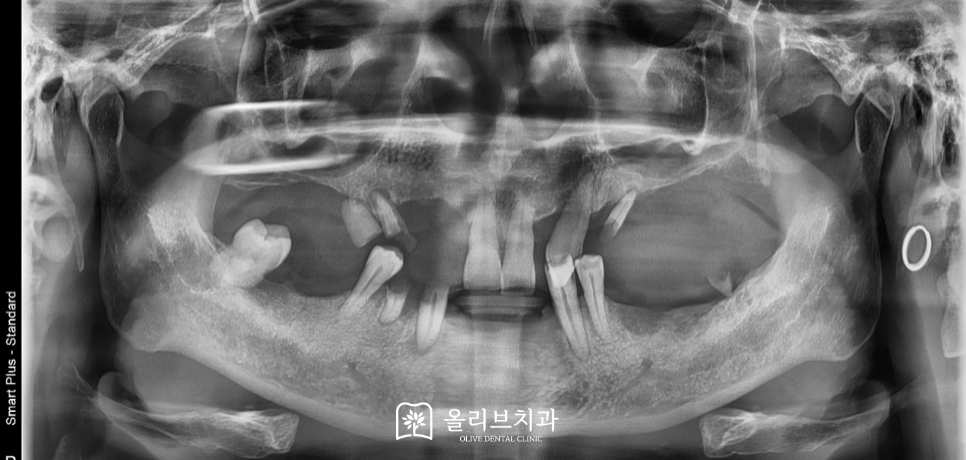

이번에 저희 비산동임플란트 올리브치과에 내원하신 환자분은 50대 후반의 남성으로 대다수 치아가 이미 발거된 상태였습니다. 남아 있는 치아도 교합을 지탱할 수 없을 정도로 배열과 기능이 무너진 상황이었고 환자분께서도 “치과에 너무 오래되었고 지금은 밥먹기가 너무 힘들다”고 말씀하시며 큰 불편을 호소하셨습니다.

전체 x-ray를 통해 뼈의 상태와 치아의 상태를 확인하였습니다.

전체적인 진단 결과 현재 남아있는 치아는 전혀 살려서 사용할 수 없는 상태였고 특히 상악 구치부에는 치조골이 많이 소실되어 있어 일반적인 방법으로는 임플란트 식립이 어려운 상태였습니다. 이에 따라 상악동 거상술을 함께 진행하며 충분한 뼈를 확보한 후 골 상태에 맞는 최적의 위치에 임플란트를 계획적으로 식립하기로 하였습니다. 전체적인 모든 치료는 한 번에 끝나는 이 아니라 필요한 진료들을 차근차근 단계적으로 진행하였습니다.